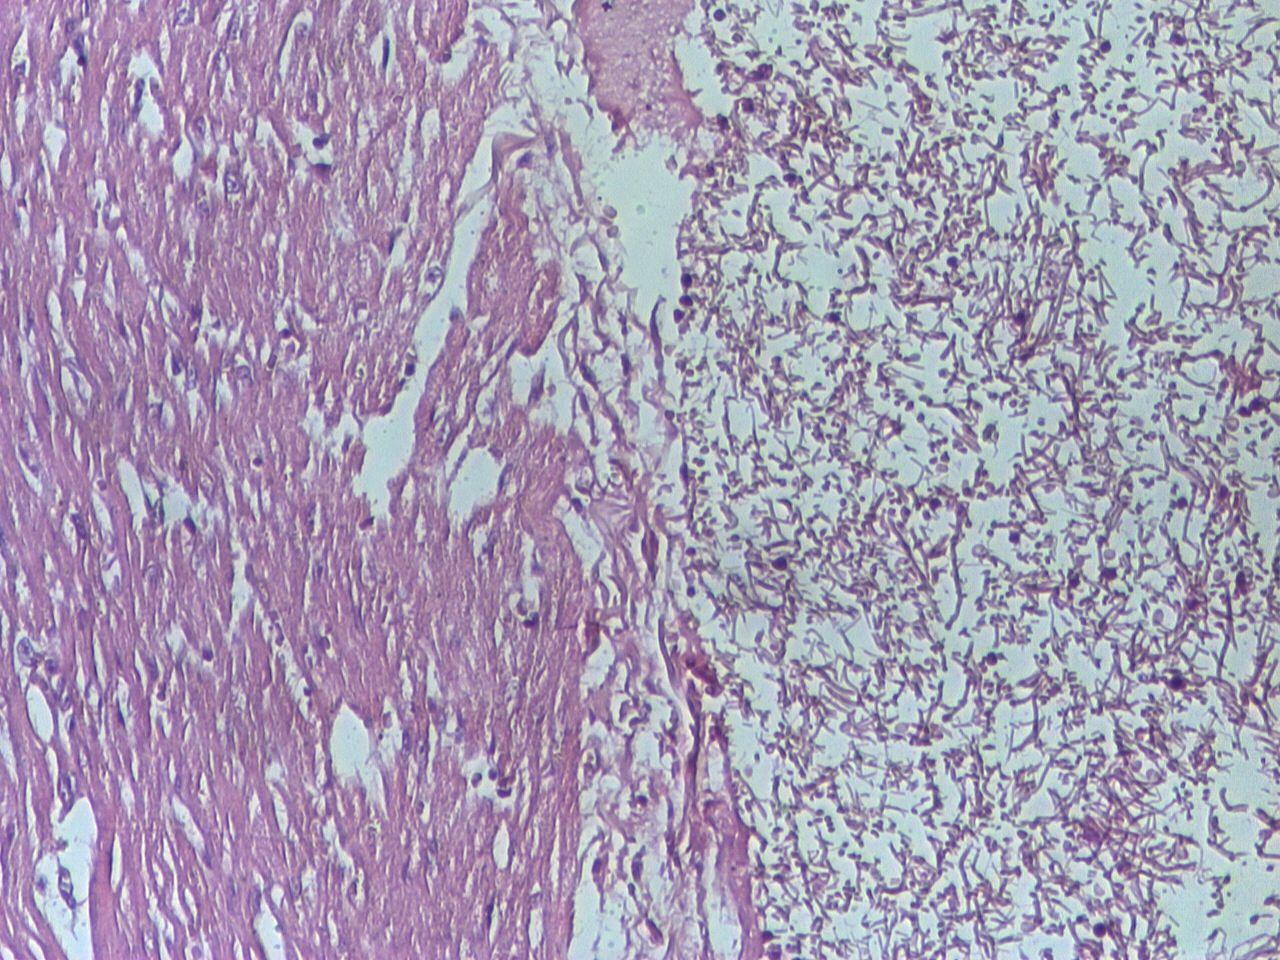

Miocardita este inflamația mușchiului cardiac, care poate apărea în contextul unor infecții, reacții imune sau expuneri la factori toxici. Inflamația afectează integritatea și funcția celulară a miocardului și poate influența atât capacitatea de pompare a inimii, cât și stabilitatea ritmului electric; manifestările clinice pot varia semnificativ între persoane, de la simptome subtile la tulburări mai severe. Descrierea cauzelor și mecanismelor este complexă și în evoluție, iar abordarea terapeutică este adaptată în funcție de severitate și de contextul clinic.

Inflamația mușchiului cardiac poate avea origini variate; frecvent este asociată cu răspunsuri inflamatorii după infecții, dar și expunerea la anumite toxine, reacțiile autoimmune sau efectele secundare ale unor medicamente pot contribui la declanșarea procesului. Mecanismele implicate sunt complexe și includ atât agresiune directă a agentului cauzal asupra celulelor cardiace, cât și activarea unei reacții imune care poate persista și agrava leziunea.

În cazuri selectate se recurge la teste avansate: rezonanță magnetică cardiacă – care poate contribui la identificarea inflamației și a modificărilor structurale, monitorizare ambulatorie Holter pentru aritmii, teste virologice sau autoimune după contextul clinic, iar biopsia endomiocardică rămâne o opțiune rezervată situațiilor în care rezultatul poate influența conducerea terapeutică. Evaluarea este individualizată și implică reevaluări periodice; dacă apar simptome noi sau se agravează starea, este important să contactați echipa medicală. Resurse suplimentare: /?s=miocardita